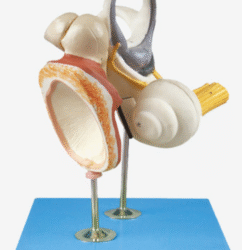

ATL-112 KNEE JOINT INTRACAVITY INJECTION SIMULATOR SOFT

Made of imported polymer materials, clear layers of skin and muscle, with integrated knee anatomical structure, and manifest body surface symbols

Features:

1. Can puncture repeatedly, standard puncture sites facilitate to acupuncture and there is realistic feeling when needle inserts into veins

2. A single valve can inject simulated liquid of bursa mucosa into bursa mucosa repeatedly

3. Automatic sealing of bursa mucosa

4. Skin surface can be cleaned by suds